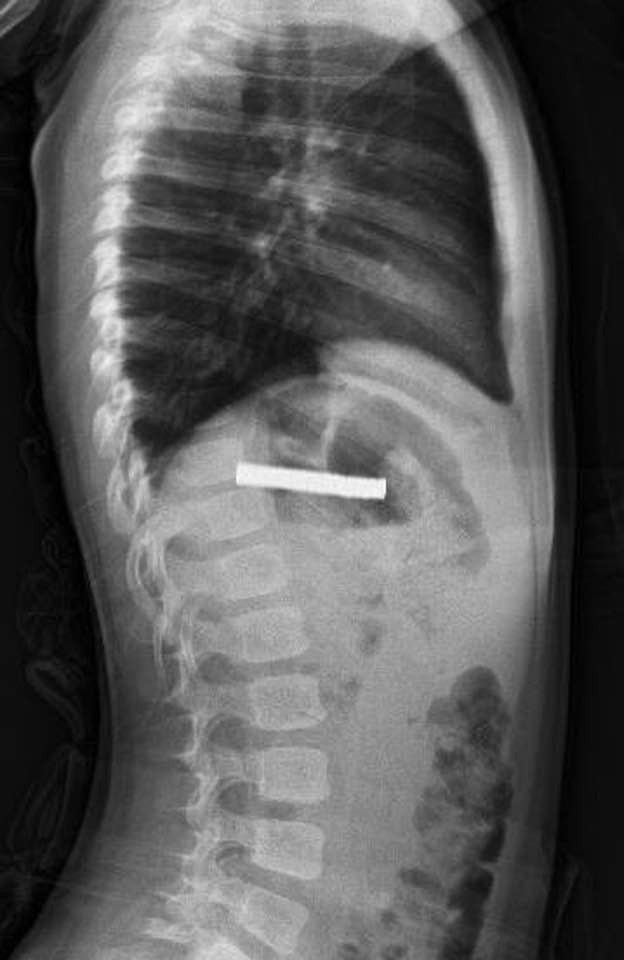

Erzurum’da yaşayan 3 yaşındaki bir çocuk, evde oynarken 19 adet küçük mıknatısı yuttu. Rahatsızlanan çocuğun durumunu fark eden ailesi, hemen hastaneye başvurdu. Yapılan ilk müdahalenin ardından küçük çocuk Elazığ’daki Fırat Üniversitesi Hastanesine sevk edildi.

Fırat Üniversitesi Çocuk Gastroenteroloji Hepatoloji ve Beslenme Bilim Dalı Başkanı Prof. Dr. Yaşar Doğan tarafından yapılan operasyonla, çocuğun yemek borusuna yapışan 19 mıknatıs endoskopik yöntemle çıkarıldı.

Mıknatısların uzun süre yemek borusunda kalması nedeniyle yemek borusu ve mide girişinde zedelenmeler oluştu. Ancak hastanede yapılan tedavinin ardından çocuğun sağlık durumunun iyi olduğu ve taburcu edildiği öğrenildi.